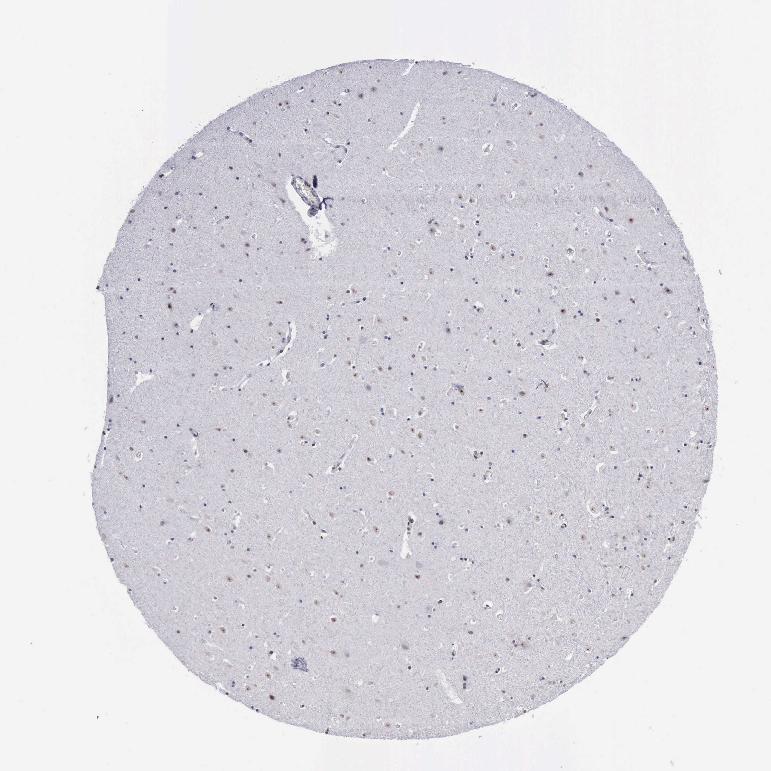

TISSUE PRIMARY DATA HIPPOCAMPUS Show tissue menu

HIPPOCAMPUS - Antibody stainingi

Antibody staining in the annotated cell types in the current human tissue is reported as not detected, low, medium, or high, based on conventional immunohistochemistry profiling in selected tissues. This score is based on the combination of the staining intensity and fraction of stained cells.

Each image is clickable and will lead to virtual microscopy that enables deeper exploration of all samples and also displays staining intensity scores, fraction scores and subcellular localization as well as patient and tissue information for each sample.

Antibody HPA001119Antibody CAB009392

Glial cells Not detectedNot detected

Neuronal cells Not detectedMedium